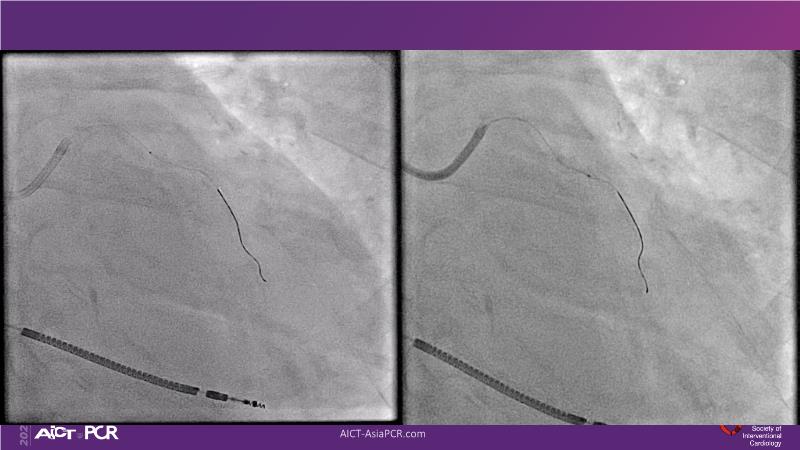

Cracking calcium: best practices to integrate intravascular lithotripsy into your calcium management algorithm

With this session, keep up to date on the evidence, trials and outcome data for intravascular lithotripsy in severely calcified lesions. Learn how to use this technique in real-world patients and understand its role in the treatment algorithm for severely calcified coronary lesions.

- To learn how to use intravascular lithotripsy in real-world patients with severely calcified coronary lesions